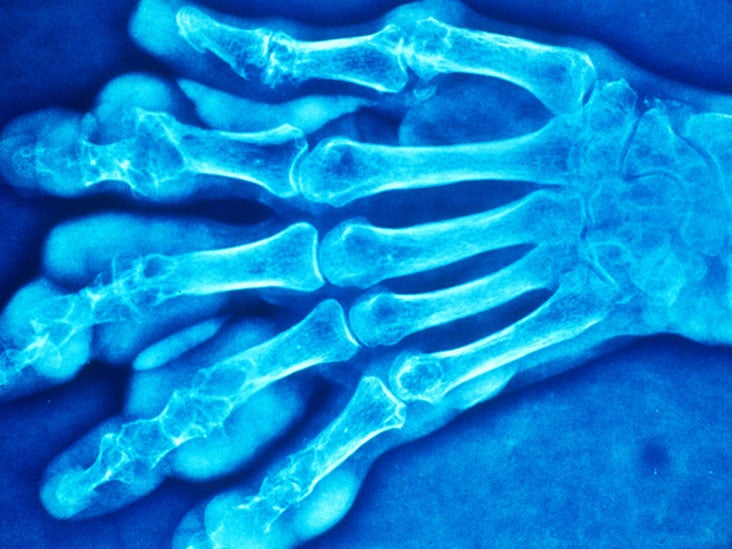

From www.sciencephoto.com

The hand of a patient affected by gout Stock Image M165/0103 Can A Person Get Gout In Their Thumb Gout is a condition that causes sudden, excruciating pain and swelling in the affected joints, particularly in the big toe. However, the hands are a common site for subsequent. A gout attack in the thumb can be extremely painful because of how often you use your thumbs, from turning doorknobs to writing. Gout is a common and complex form of. Can A Person Get Gout In Their Thumb.

Gout affecting the hand Stock Image C045/9579 Science Photo Library Can A Person Get Gout In Their Thumb Gout typically develops in one joint at a time, especially. Is it possible for a person to develop gout in their hands? It's characterized by sudden, severe attacks of pain, swelling, redness and tenderness in one or more. A gout attack in the thumb can be extremely painful because of how often you use your thumbs, from turning doorknobs to. Can A Person Get Gout In Their Thumb.